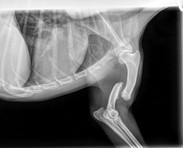

Unser kleiner Yoko, ein junger Yorki- Mischling (geb. 2024), hat sich beim Spielen mit seinen Hundefreunden schwer verletzt. Am vergangenen Mittwoch brach er sich beim Toben im Auslauf überraschend den linken Vorderlauf – ein schmerzhafter und dramatischer Moment für alle Beteiligten.

Unsere Kollegin eilte sofort zu ihm und umgehend brachten wir ihn hier zum Tierarzt. Dort stellten die Ärzte nach dem Röntgen einen Bruch von Radius und Ulna fest. Die Verletzung war so schwer, dass eine spezialisierte Operation in einer Tierklinik nötig wurde.

Bereits am Freitagmorgen fuhr Yoko in die Klinik – und am Nachmittag konnten wir ihn zum Glück wieder in die Arme schließen. Die Operation war erfolgreich: Eine Osteosynthese mit einer 2mm Knochenplatte war notwendig.

Doch damit ist es nicht getan – in der nächsten Zeit benötigt er Schmerzmittel, strikte Leinenruhe, Physiotherapie und einige Zeit später eine zweite OP, um die Platte wieder zu entfernen.

Die geschätzten Gesamtkosten: ca. 4.000 €